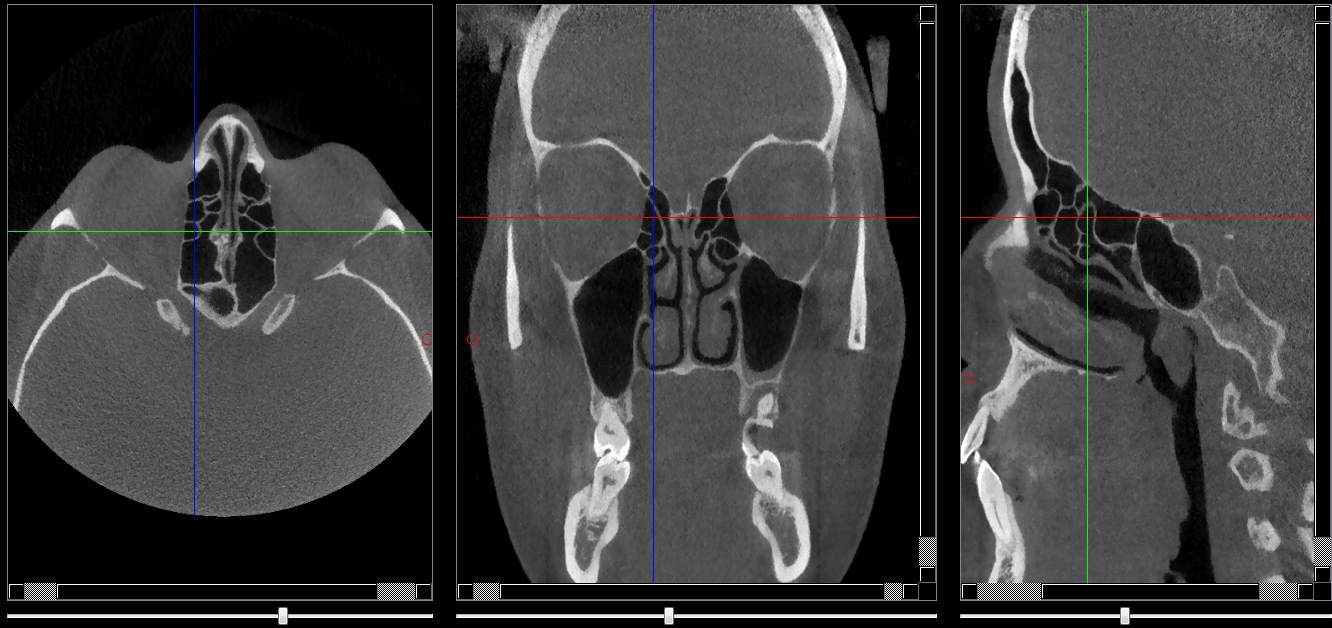

Structures osseuses

Bulle ethmoïdale

Repères anatomiques

- Coupe transversale

- Début : Fissure orbitaire sup

- Fin : Cornet nasal moyen

- Coupe frontale

- Début : Septum nasal

- Fin : Cornet nasal moy

- Coupe saggitale

- Début : Sinus maxillaire

- Fin : Septum nasal